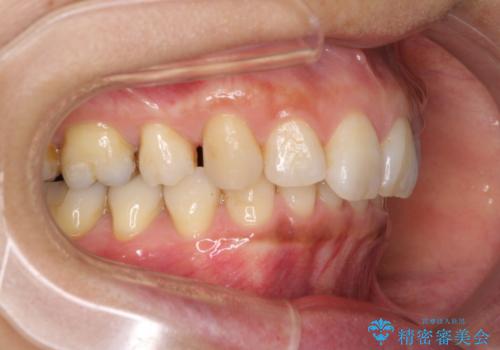

抜歯矯正の後戻りでできたスペース インビザライン矯正とセラミック治療

- 以前行った抜歯矯正が後戻りし、開いてしまったスペースが気になるとのことで来院された患者様です。

インビザラインを用いて開いてしまったスペースと前歯のデコボコを改善することとしました。

上顎前歯を左右対称となるように歯列を整えたいとのことでしたが、すり減って形態が大きく異なっていたため、できる範囲での仕上がりとなりました。